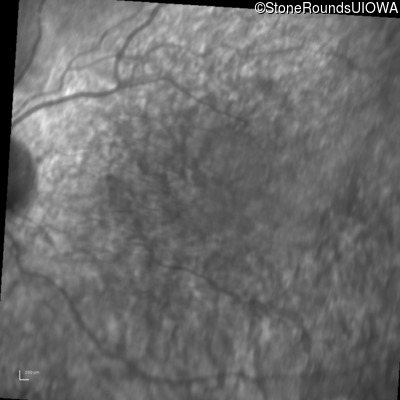

Infrared Fundus Photograph - Left - 20/40 -1

Exemplar